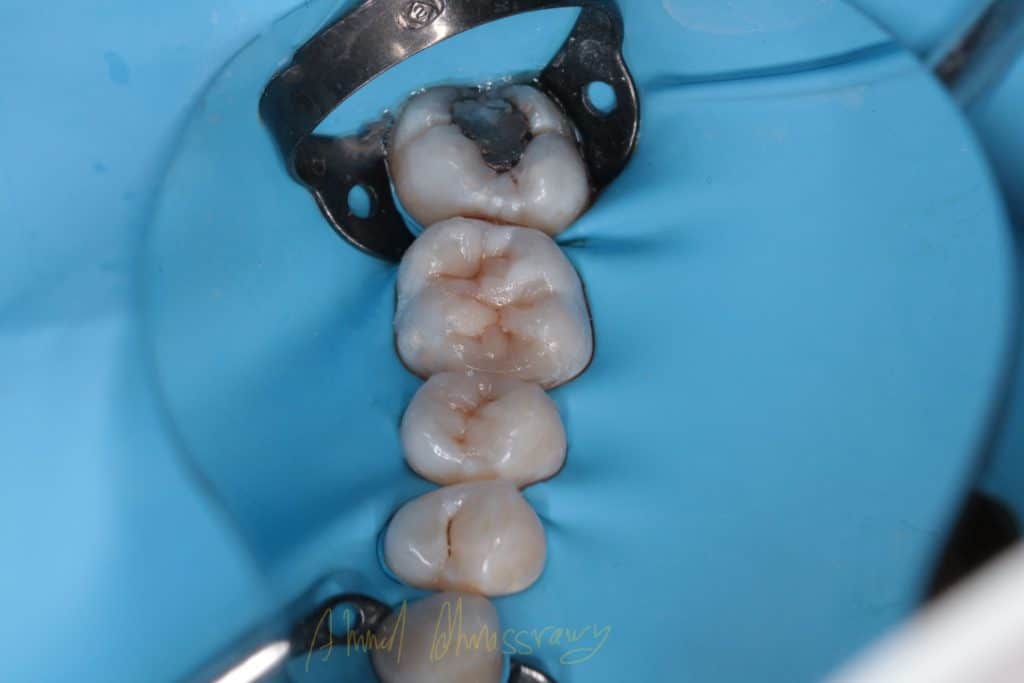

remove old restoration

cavity design